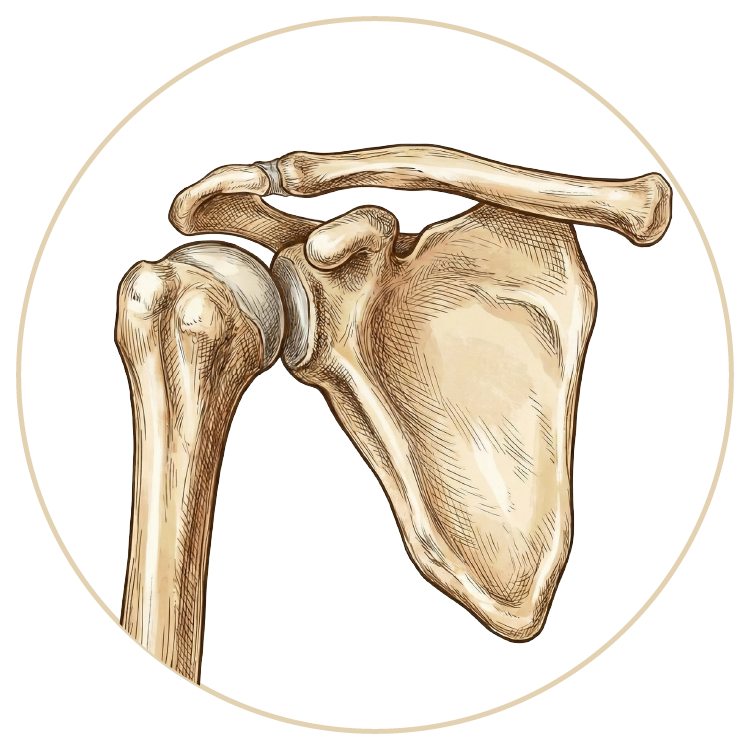

Omuz Hastalıkları ve Tedavileri

Omuz Hastalıkları